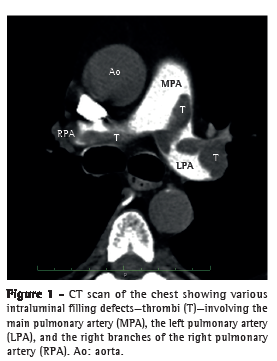

A 63-year-old man presented to the Pablo Tobon Uribe Hospital, in Medellin, Colombia, complaining of dyspnea in the preceding two weeks. Physical examination revealed tachycardia, tachypnea, mild hypertension, jugular venous distention, abdominal distention, and edema in the lower limbs. However, cardiac and pulmonary findings were unremarkable. An electrocardiogram revealed only sinus tachycardia. The cardiac troponin I level was 0.2 ng/mL (normal, < 0.04 ng/mL), and the N-terminal pro-brain natriuretic peptide level was 3,590 pg/mL (normal, < 125 pg/mL). Subsequent helical CT scans of the chest confirmed PE by showing filling defects involving the main pulmonary artery and its primary branches (Figure 1). A venous ultrasound revealed left iliofemoral deep vein thrombosis. Intravenous heparin was started.